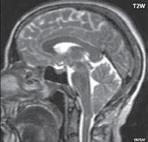

Chiari I: CT a MR zobrazí malou zadní jámu lební, absenci cisteren zadní jámy lební, pokles tonzil, krátký a konkávní klivus, poruchu cirkulace mozkomíšního moku v oblasti foramen magnum a následný hydrocefalus. MR navíc může prokázat edém krční míchy a ve vysokém procentu případů hydrosyringomyelii.

Chiari II: CT a MR zobrazí malou zadní jámu lební, absenci nebo výraznou redukci cisterny cerebelomedulární a dalších kmenových cisteren, konkávní klivus. Mohou být abnormality v oblasti foramen okcipitale magnum, nízký úpon tentoria, někdy absence nebo fenestrace falx cerebri. MR lépe ukáže kaudálně uloženou a protáhlou IV. komoru (někdy je přirovnávána až ke stéblu slámy), protažený pons a další možné, přidružené abnormality (hydrosyringomyelii, agenezi, hypogenezi nebo fenestraci corpus callosum…).